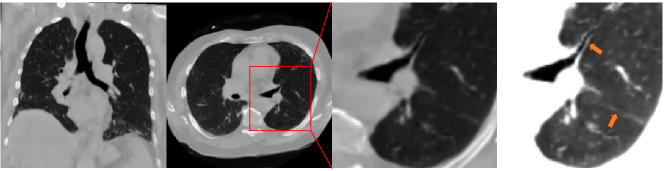

Refer to caption

Figure 3: Randomly generated images (from HA-GAN and Medical Diffusion) and the real images. The first two columns show axial and coronal slices, which use the HU range of [-1024, 600]. The last column shows the zoom-in region and uses HU range of [-1024, -250] to highlight the lung details. Our method is the only one that can preserve delicate anatomical details, including fissures, as indicated by the arrows.

Quantitative Evaluation on Anatomical Details: While metrics like FID and MMD are widely used in literature and empirically work well for natural images, they highlight the semantic-wise similarly (distance) but may ignore subtle but important anatomical details in medical images, as implied by the small (FID/MMD) gap between different methods. Their real distances, as later shows in Fig. 3, could be much bigger when taking account into the anatomical details we are focused on. Therefore, we evaluate how well the generated images can preserve the anatomical details. Specifically, we use Total Segmentor [34] to segment vessels and airways from generated images and real images, and measure the volume. The results are shown in Table. 1. We also perform statistical tests (one-tailed two-sample t-test) on the evaluation results. At the significance level of p<0.05𝑝0.05p<0.05, the results are significant for all three conditions, which further identify the effectiveness of our model on prompting generation.

5.2.2 Qualitative Evaluation

To qualitatively analyze the results, we show cases of synthetic images from current best baseline GAN [6] and diffusion model [20]. Asin Fig. 3, although synthetic images from different methods are all closed to the real ones in overall appearance, only our MedSyn consistently produces anatomically plausible CT scans upon closer inspection, showcasing its superiority.